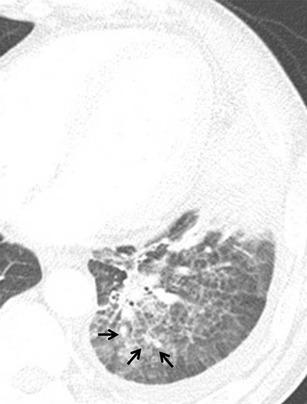

Thoracic actinomycosis can be radiologically divided into the parenchymal type, the airway type including bronchiectasis, the endobronchial form, and the mediastinum or chest wall involvement type.

• Important risk factors for thoracic actinomycosis are underlying respiratory disorders such as emphysema and chronic bronchitis. • Different CT patterns can be distinguished in thoracic actinomycosis: parenchymal, bronchiectatic, endobronchial and extrapulmonary. • Typical CT findings in the parenchymal pattern are a central low density within the parenchymal consolidation and adjacent pleural thickening.

胸放线菌病可在放射学上分为实质型、气道型(包括支气管扩张)、支气管内型和纵隔或胸壁受累型。

• 胸放线菌病可区分不同的 CT 模式:实质型、支气管扩张型、支气管内型和肺外型。